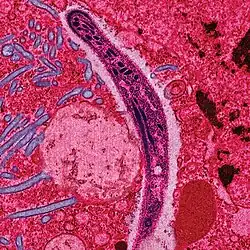

Malaria parasites are transmitted by female Anopheles mosquitoes. The parasites multiply within red blood cells, causing symptoms that include symptoms of anemia (light headedness, shortness of breath, tachycardia etc.), as well as other general symptoms such as fever, chills, nausea, flu-like illness, and in severe cases, coma and death. Malaria transmission can be reduced by preventing mosquito bites with mosquito nets and insect repellents, or by mosquito control by spraying insecticides inside houses and draining standing water where mosquitoes lay their eggs.

Within the red blood cells the parasites multiply further, again asexually, periodically breaking out of their hosts to invade fresh red blood cells. Several such amplification cycles occur. Thus, classical descriptions of waves of fever arise from simultaneous waves of merozoites escaping and infecting red blood cells.